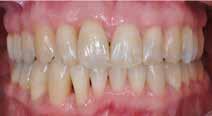

Den kliniske undersøgelse viser harmoniske ekstraorale sagittale forhold med skeletalt dybt bid (Fig. 1A, D). Hendes smil er alderssvarende med en eksponering på 8/10 af overkæbeincisiverne, mens smilets bredde er smalt med synlige mørke laterale rum (Fig. 1D). Underkæbeincisiverne er synlige under tale. Der ses neutrale okklusale forhold ved hjørnetænderne og neutrale pladsforhold i overkæben, men udtalt trangstilling i underkæben især lokaliseret i regio 1-1 (Fig. 1C).

Sliddet klassificeres som grad 2 (moderat tandslid) på de centrale incisiver i overkæbe og underkæbe. Det kan anses som patologisk, da det er atypisk for patientens alder, giver anledning til smerte/ubehag, og giver patienten et æstetisk problem. Der ses infraktioner af overkæbeincisiverne. Der ses endvidere en udtalt Spee-kurve i underkæben og ingen interincisal afstøtning på 2-2 med let ganepåbidning.

Røntgenanalyse viser fravær af -6 samt et velholdt tandsæt uden tegn på sygdom. Profilrøntgenbilledet viser et skeletalt

dybt bid, men normal inklination af fortænder i over- og underkæbe (Fig. 1B).

Fig. 5. A, B. Smil og kæbeforhold før og efter. Et bredere smil med korrektion af de laterale mørke rum. C-F. Harmonisk hældning af overkæbe- og underkæbeincisiver, rekonstruktion af den tabte tandsubstans efter nivellering af gingivaniveau og optimal bukko-lingval placering til direkte plastbehandling.

5. A, B. Smile and jaw relationships before and after. A wider smile with correction of the lateral dark spaces. C-F. Harmonious inclination of the upper and lower jaw incisors, reconstruction of the lost tooth substance after leveling the gingival level, and optimal bucco-lingual positioning for direct plastic treatment.